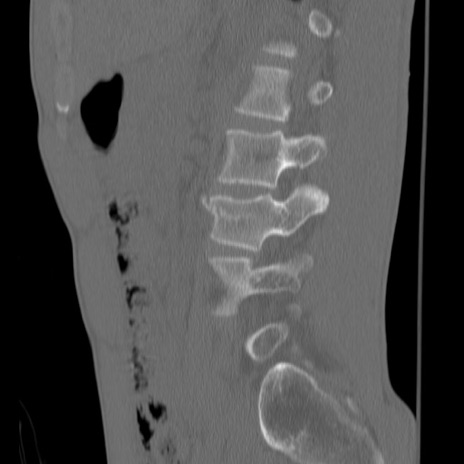

症例3 腰椎CT(矢状断像)

【症例】30歳代男性

【主訴】腰痛

【現病歴】本日旅行先で観光中に、友人と衝突し転倒し受傷。

【身体所見】麻痺なし、右下腿内側前面外側、左下腿内側に知覚鈍麻・しびれ

異常所見と診断は?

腰椎CT